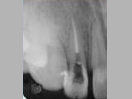

An unconventional way of treating Non-Vital Tooth with Apical Pathology with the help of MTA (Mineral Trioxide Aggregate)

Dead discolored tooth

with a growth in bone

In the process of

saving tooth by

Root Canal Treatment

MTA is placed in

the apical 5mm

of  Root Canal.

Rest part kept empty.

X-ray

Pre-Operation

After 3 months

x-ray post operation

After 2 years